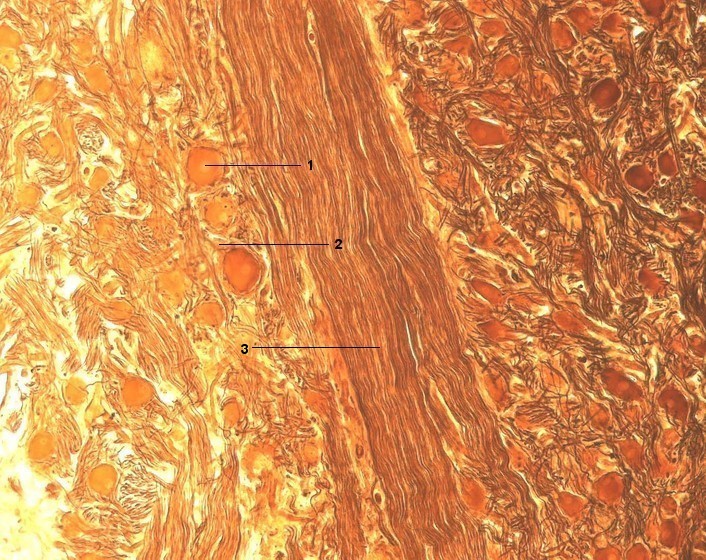

1 Multipolare Nervenzelle, Perikaryon

2 Dendrit einer Nervenzelle

3 Nervenfaserbündel